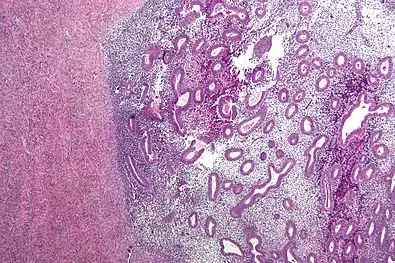

Micrograph showing endometriosis (right) and ovarian stroma (left)

Micrograph of the wall of an endometrioma. All features of endometriosis are present (endometrial glands, endometrial stroma and hemosiderin-laden macrophages).